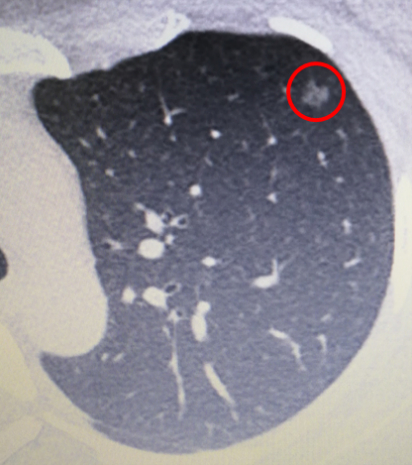

骨科手术术前胸部CT检查发现“隐藏”的早期肺癌

张小姐是一位26岁的律师事务所白领,因骨科疾病需要手术治疗,专门到暨南大学附属第一医院关节外科住院,胸部CT意外发现左上肺一个毛玻璃结节(GGO),直径接近1cm,高度怀疑早期肺癌。对此,张小姐非常困惑,听闻肺癌都是中老年人才会得病,而且很多人都是长期抽烟的“老烟枪”,而自己生活规律又健康,且从不抽烟,为何还招惹肺癌呢?  图中红色圆圈内为肺部毛玻璃结节(GGO) 其实,年纪轻轻便患上肺癌早已不是罕见事儿,尤其是胸部CT作为常规体检项目后,早期发现肺癌的比例有所增长。幸运的是,由于发现得早并及时行微创手术治疗,张小姐术后恢复非常好,和普通人的寿命没有多大差别。

蔡松旺表示,事实上,绝大多数的肺结节是炎症增殖病灶,属于良性病变,因此不用过于担心。只有5%左右的才是肺癌,这时候才考虑手术治疗。而毛玻璃结节(GGO),尤其是混杂了实性成分的毛玻璃结节,一定不能大意,不要觉得自己离肺癌很远,一定要请胸外科医生进行评估,看是否需要手术切除还是继续观察。

另外,蔡松旺再次提醒:成年人体检时一定要选择行胸部CT检查,即使你很年轻。目前的研究表明,肺部毛玻璃结节(GGO)好发于女性,不抽烟或者偶尔抽烟。早期发现,早期治疗,通常疗效都很好,避免悲剧的发生。